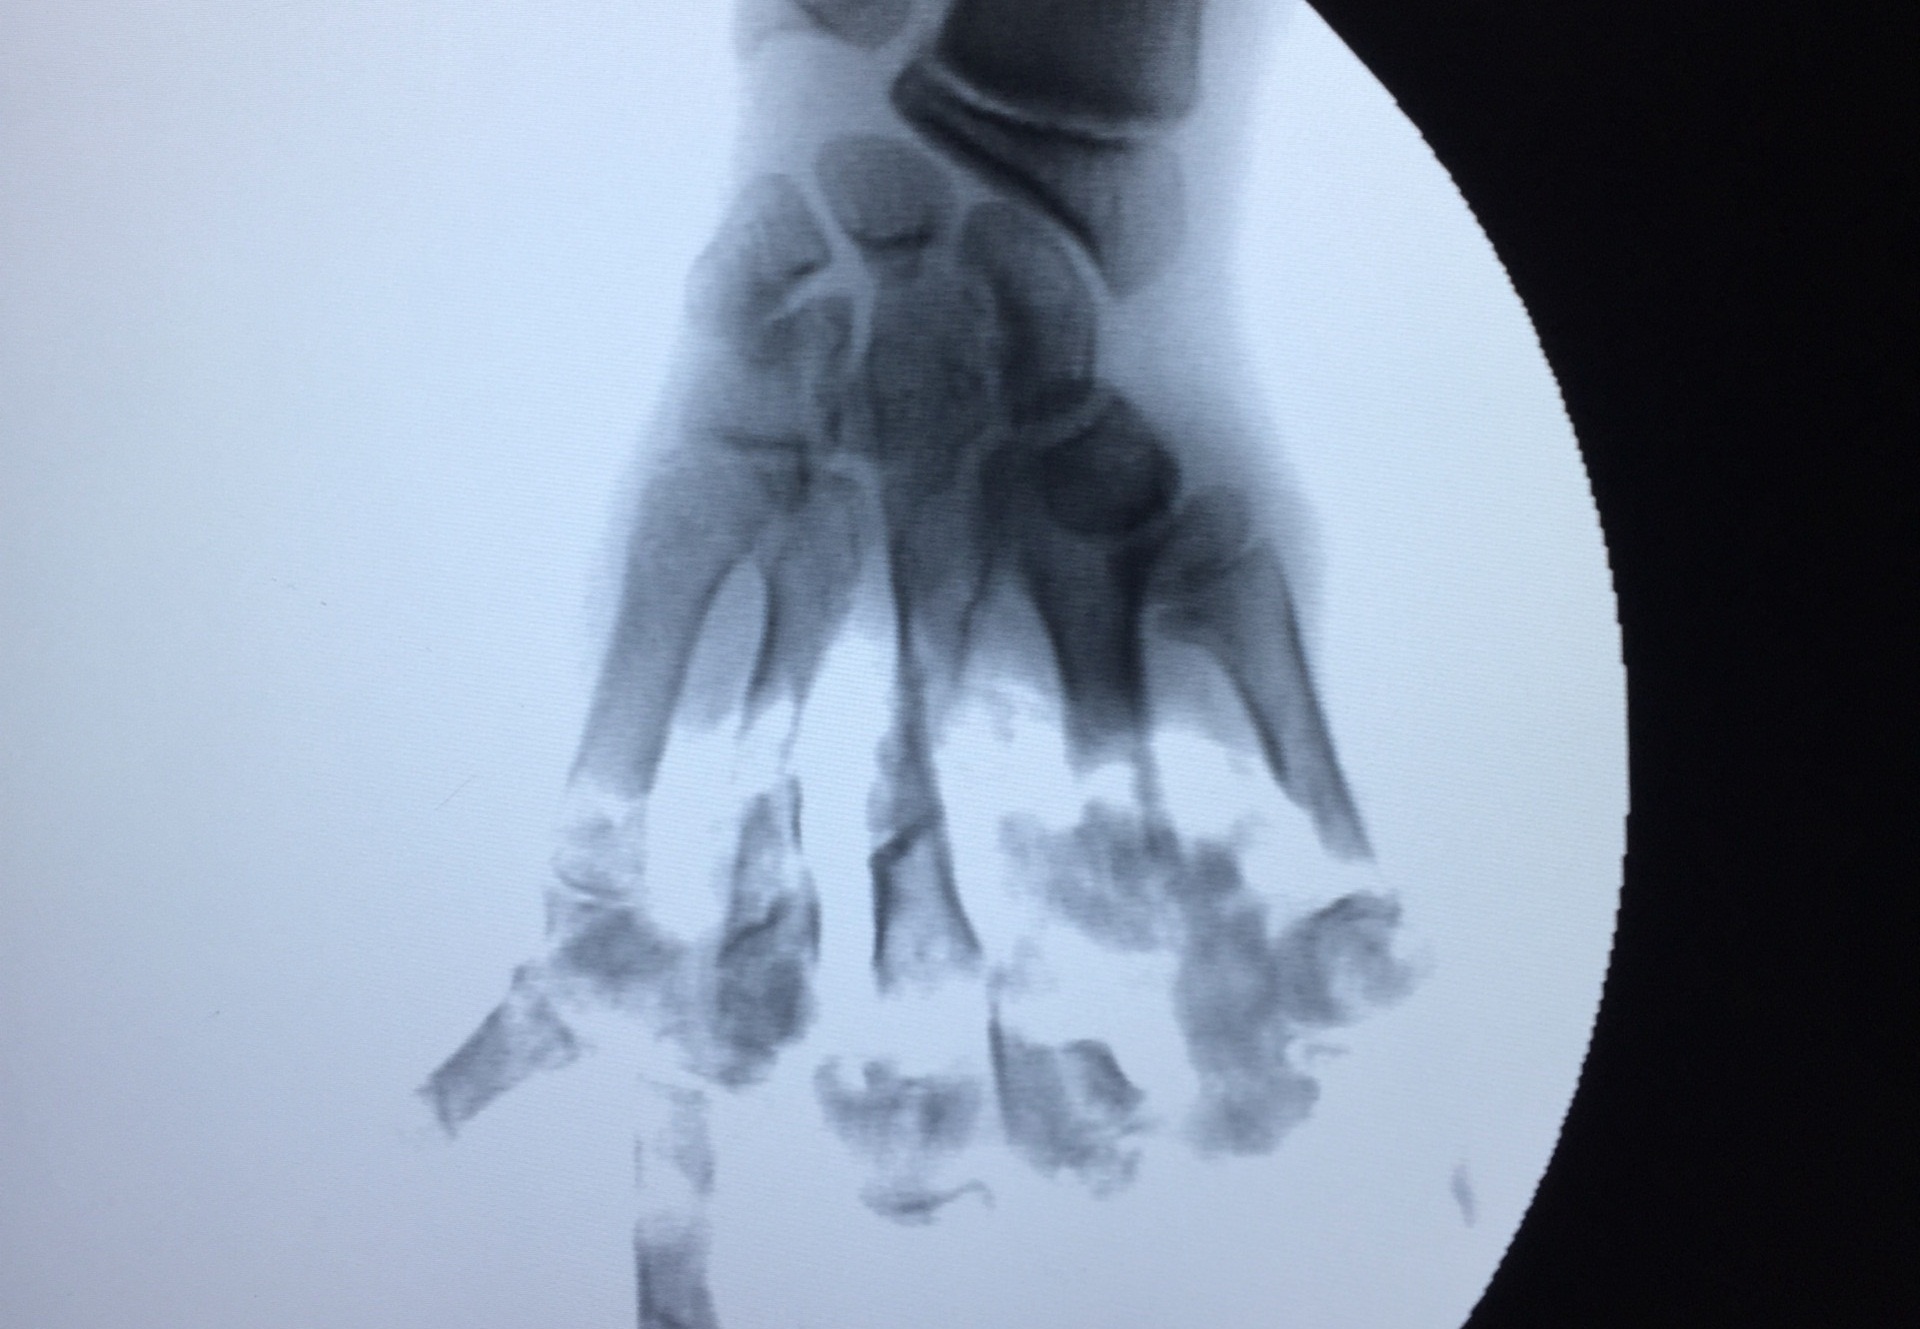

Qua chụp X-quang, cho thấy hình ảnh các đốt xương 5 ngón tay bị nghiền nát, cụt hết xương bàn ngón. Bệnh nhân được chỉ định cắt lọc tạo mỏm cụt 1/2 bàn tay và tiêm thuốc giảm đau.

| Hình ảnh phim chụp bàn tay của nạn nhân. Ảnh: Tùng Chi. |